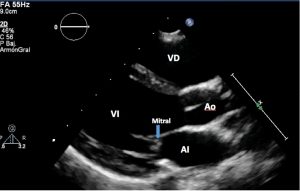

Plano longitudinal paraesternal largo

– Posición de la sonda: la situaremos a nivel del 2º-3er espacio intercostal izquierdo (en neonatos sería en 3er-4º espacio), ligeramente separado del esternón, con la muesca del transductor orientada hacia la derecha del niño, realizando ligeros movimientos de rotación horaria y basculación cefálica.

– En este plano podremos realizar la medición de las dimensiones cardiacas, ventriculares y de la aurícula izquierda (AI): para obtener un adecuado plano paraesternal eje largo debemos visualizar de forma simultánea las válvulas mitral y aórtica, posicionando el tabique interventricular y la arteria aorta ascendente lo más horizontal posible en la pantalla. La valoración del anillo aórtico se debe realizar en diástole (válvula aórtica abierta), midiendo anillo, la parte más ancha que corresponde el nivel de los Senos de Valsalva y la unión sino-tubular (unión de los senos con la raíz aórtica).

Para la función del ventrículo izquierdo (VI) seleccionamos el modo M, haciendo que la línea punteada de referencia “atraviese” de forma perpendicular el tabique interventricular. Las medidas se toman al final de la diástole (telediástole) y en la sístole.

La medición del diámetro diastólico (DDVI) y sistólico (DSVI) del VI permitirá calcular la fracción de acortamiento (FA), forma rápida y fiable de la función sistólica mediante la siguiente fórmula: FA (%) = DDVI – DSVI / DDVI × 100 (valores normales: 28-44%)

Otra fórmula para la función sistólica es la Fracción de eyección (FE) (%) por Teichholz: V= 7/ (2,4 + D) xD3 (Normal > 55%) (ver siguientes lecciones).